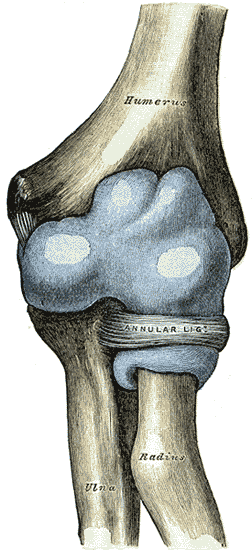

Joint capsule

The elbow joint and the superior radioulnar joint are enclosed by a single fibrous capsule. The capsule is strengthened by ligaments at the sides but relatively weak in front and behind.[7]

Synovial membrane

The synovial membrane of the elbow joint is very extensive. On the humerus, it extends up from the articular margins and covers the coronoid and radial fossae anteriorly and the olecranon fossa posteriorly. Distally, it is prolonged down to the neck of the radius and the superior radioulnar joint. It is supported by the quadrate ligament below the annular ligament where it also forms a fold which gives the head of the radius freedom of movement.[7]

Several synovial folds project into the recesses of the joint.[7] These folds or plicae are remnants of normal embryonic development and can be categorized as either anterior (anterior humeral recess) or posterior (olecranon recess).[8] A crescent-shaped fold is commonly present between the head of the radius and the capitulum of the humerus. [7]

On the humerus there are extrasynovial fat pads adjacent to the three articular fossae. These pads fill the radial and coronoid fossa anteriorly during extension, and the olecranon fossa posteriorly during flexion. They are displaced when the fossae are occupied by the bony projections of the ulna and radius.[7]